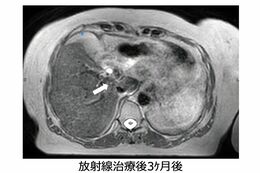

放射線治療後3か月では、ほとんどがんが見えなくなっている(画像提供:GenesisCare)

[写真 4/6枚目] 放射線治療後3か月では、ほとんどがんが見えなくなっている(画像提供:GenesisCare)